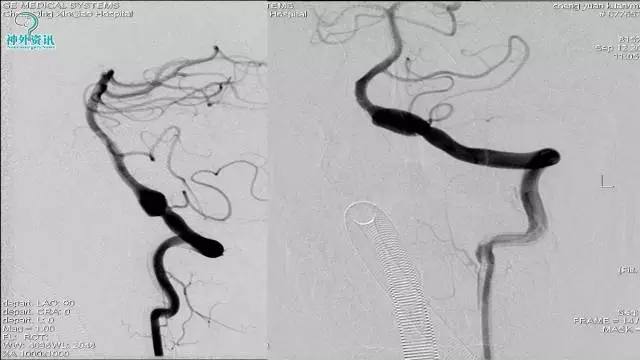

今天为大家分享的是“强生医疗CNV-神经介入专栏”第三十六期,由重庆第三军医大学附属新桥医院神经外科刘俊带来的“Galaxy弹簧圈在不规则动脉瘤中的临床应用”精彩讲课视频及PPT,欢迎观看。文章仅代表作者个人观点,如有不同见解,欢迎同道斧正!